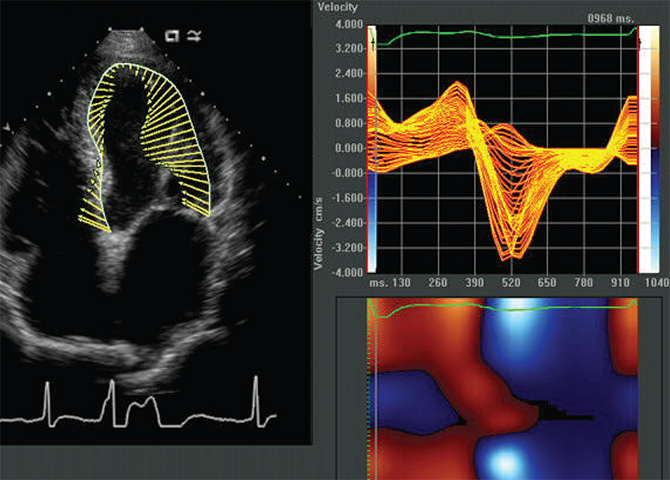

Ekokardiyografi

Ekokardiografî ses dalgaları kullanılarak gerçekleştirilen bir görüntüleme testidir. Eko kalp kasınızın ve kalp kapaklarınızın nasıl çalıştığını gösterir. Aynı zamanda kalp genişliğinizin ne kadar olduğu konusunda da bilgi verir. Ekoişlemi sırasında kullanılan ve Ultrasona bağlı bir probe ile...Devamı İçin Tıklayın

Ekokardiyografi,Eko,2.EL Eko,2.El Ultrason ,TEE probe,Kardiyak probe